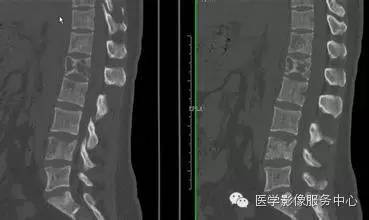

脊柱

神经母细胞瘤也常侵犯脊柱,特别是所谓的哑铃状肿瘤可侵蚀破坏椎体,椎体呈现大小不等的溶骨性改变,压缩变扁,边缘毛糙不齐且模糊。有时也显示骨质增生,椎体前后缘凹陷。